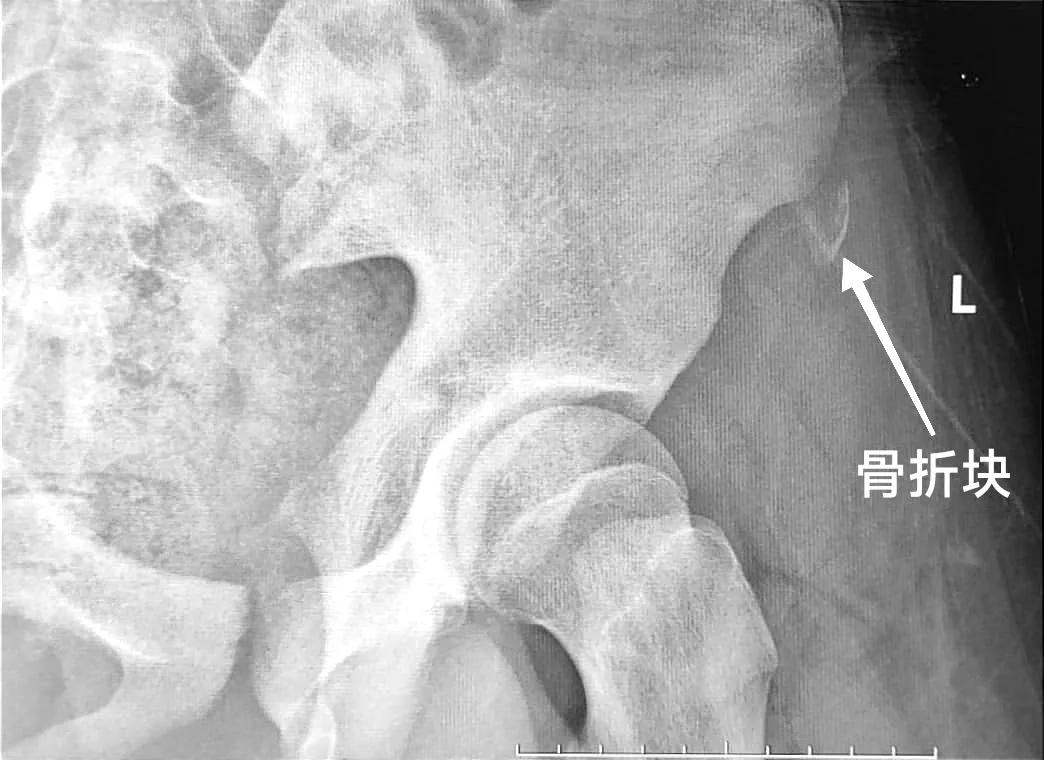

拍片一看,是“髂前上棘撕脱性骨折”。

髂前上棘撕脱性骨折多好发于青少年,这个部位有个骨骺线,是生长发育中骨头生长的部位,比较薄弱。

在髂前上棘的骨面上,有一块肌肉附着于此——“缝匠肌”,这块肌肉的作用是能够让大腿弯起来的。

当参加剧烈运动时,骨面上附着的缝匠肌突然收缩、牵拉,就容易把止点处的骨块拉下来,比如踢足球、跳远、跳高、短跑、冲刺跑、打篮球这些运动过程中,突然摆动大腿使其伸直或髋部屈曲,加之收腹的动作,这时候会使缝匠肌张力突然增加或者缝匠肌突然的收缩,导致髂前上棘撕脱骨折。当发生骨折时运动员会突然感觉髂前上棘处疼痛、肿胀,大腿不敢活动,这时候要注意可能发生骨折,要及时就医。